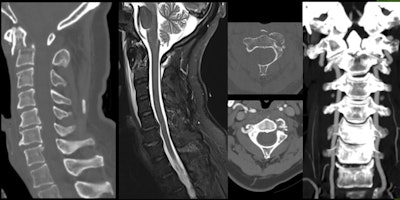

Even in the absence of skull or cervical fractures, patients may present with vascular injuries, so a high degree of suspicion is required from the examiner. Mechanisms of hyperflexion, hyperextension, acceleration, or deceleration should raise a red flag and elicit a more comprehensive investigation. In the acute setting, CT angiography is preferred over MR angiography if the patient presents with one of these mechanisms and/or skull base fractures and/or cervical fractures involving the vertebral foramina.

CT of the spine highlights fractures and dislocations, raising suspicion of ligament and spinal cord injuries, but MRI has superior sensitivity for these injuries and can confirm soft tissue lesions, vertebral canal hemorrhages, and spinal cord injuries.